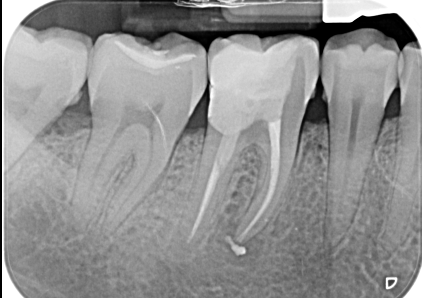

Il trattamento endodontico (devitalizzazione) consiste nel rimuovere la polpa dentaria o piu comunemente il nervo contenuto all’interno del dente e nelle sue radici, che sia infetto o infiammato.

L’obbiettivo di questa terapia è detergere, disinfettare e sigillare lo spazio lasciato libero dal nervo.

Attraverso l’esecuzione di una corretta terapia canalare si raggiunge l’obiettivo primario che è il mantenimento del dente, che dovra successivamente essere riabilitato protesicamente con corona o intarsio, all’interno del cavo orale scongiurando l’istaurarsi di infezioni e conseguentemente di dolore.